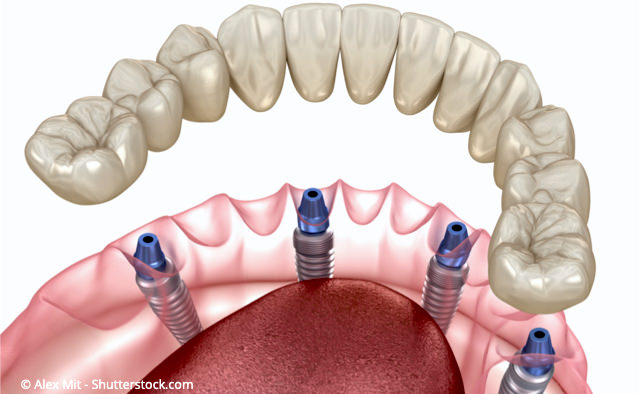

Wörtlich übersetzt bedeutet All-on-Four "Alle auf Vier".

Gemeint ist damit, dass eine ganze Zahnreihe auf nur vier Implantaten befestigt werden kann.

Bei den gängigen Implantations-Methoden werden pro Kiefer sechs bis acht Implantate benötigt, um komplett festsitzende Zähne einsetzen zu können. Bei der All-on-Four-Implantations-Methode genügen i.d.R. nur vier Implantate pro Kiefer! Diese werden in einer speziellen Anordnung gesetzt, die für eine gleichmäßige Belastung der Implantate sorgt (s.u.)

Auf nur vier Implantaten kann eine ganze Zahnreihe befestigt werden.

Die Zähne werden auf den Implantaten fest verschraubt.

Warum genügen bei dieser Methode i.d.R. vier Implantate pro Kiefer?

Vor der Implantation wird die spätere Position der Implantate mittels eines Röntgenbildes festgelegt. Damit können wir die spätere Position der Implantate zuverlässig vorausplanen.

Im vorderen Kieferbereich werden zwei parallel zueinander stehende Implantate eingesetzt. Im hinteren Kieferbereich wird auf jeder Seite ein Implantat in einem Winkel von 35 - 45 Grad eingesetzt. Diese Anordnung der Implantate sorgt neben einer hohen Stabilität für eine günstige Belastungs-Verteilung und erübrigt weitere Implantate.

Der große Vorteil der All-on-Four-Implantationsmethode ist, dass der vorhandene Kieferknochen optimal genutzt wird. Deshalb ist in den meisten Fällen kein Kieferknochenaufbau notwendig wie das bei anderen Implantationsverfahren oft der Fall ist.

Im vorderen Kieferbereich werden zwei parallel zueinander stehende Implantate eingesetzt. Im hinteren Kieferbereich wird auf jeder Seite ein Implantat in einem Winkel von 35 - 45 Grad eingesetzt. Diese Anordnung der Implantate sorgt neben einer hohen Stabilität für eine günstige Belastungs-Verteilung und erübrigt weitere Implantate.

Der große Vorteil der All-on-Four-Implantationsmethode ist, dass der vorhandene Kieferknochen optimal genutzt wird. Deshalb ist in den meisten Fällen kein Kieferknochenaufbau notwendig wie das bei anderen Implantationsverfahren oft der Fall ist.